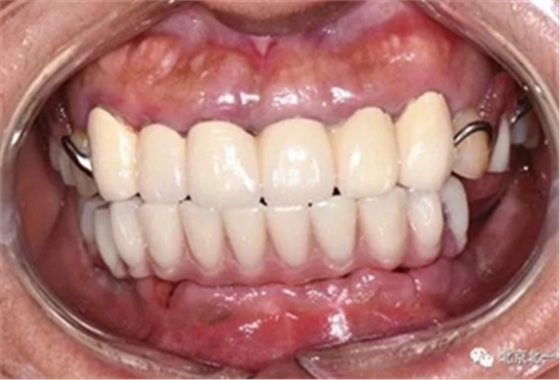

圖十四:口內(nèi)照

圖十九:永久修復(fù)完成

圖二十:永久修復(fù)咬合關(guān)系

圖二十五:口內(nèi)照。